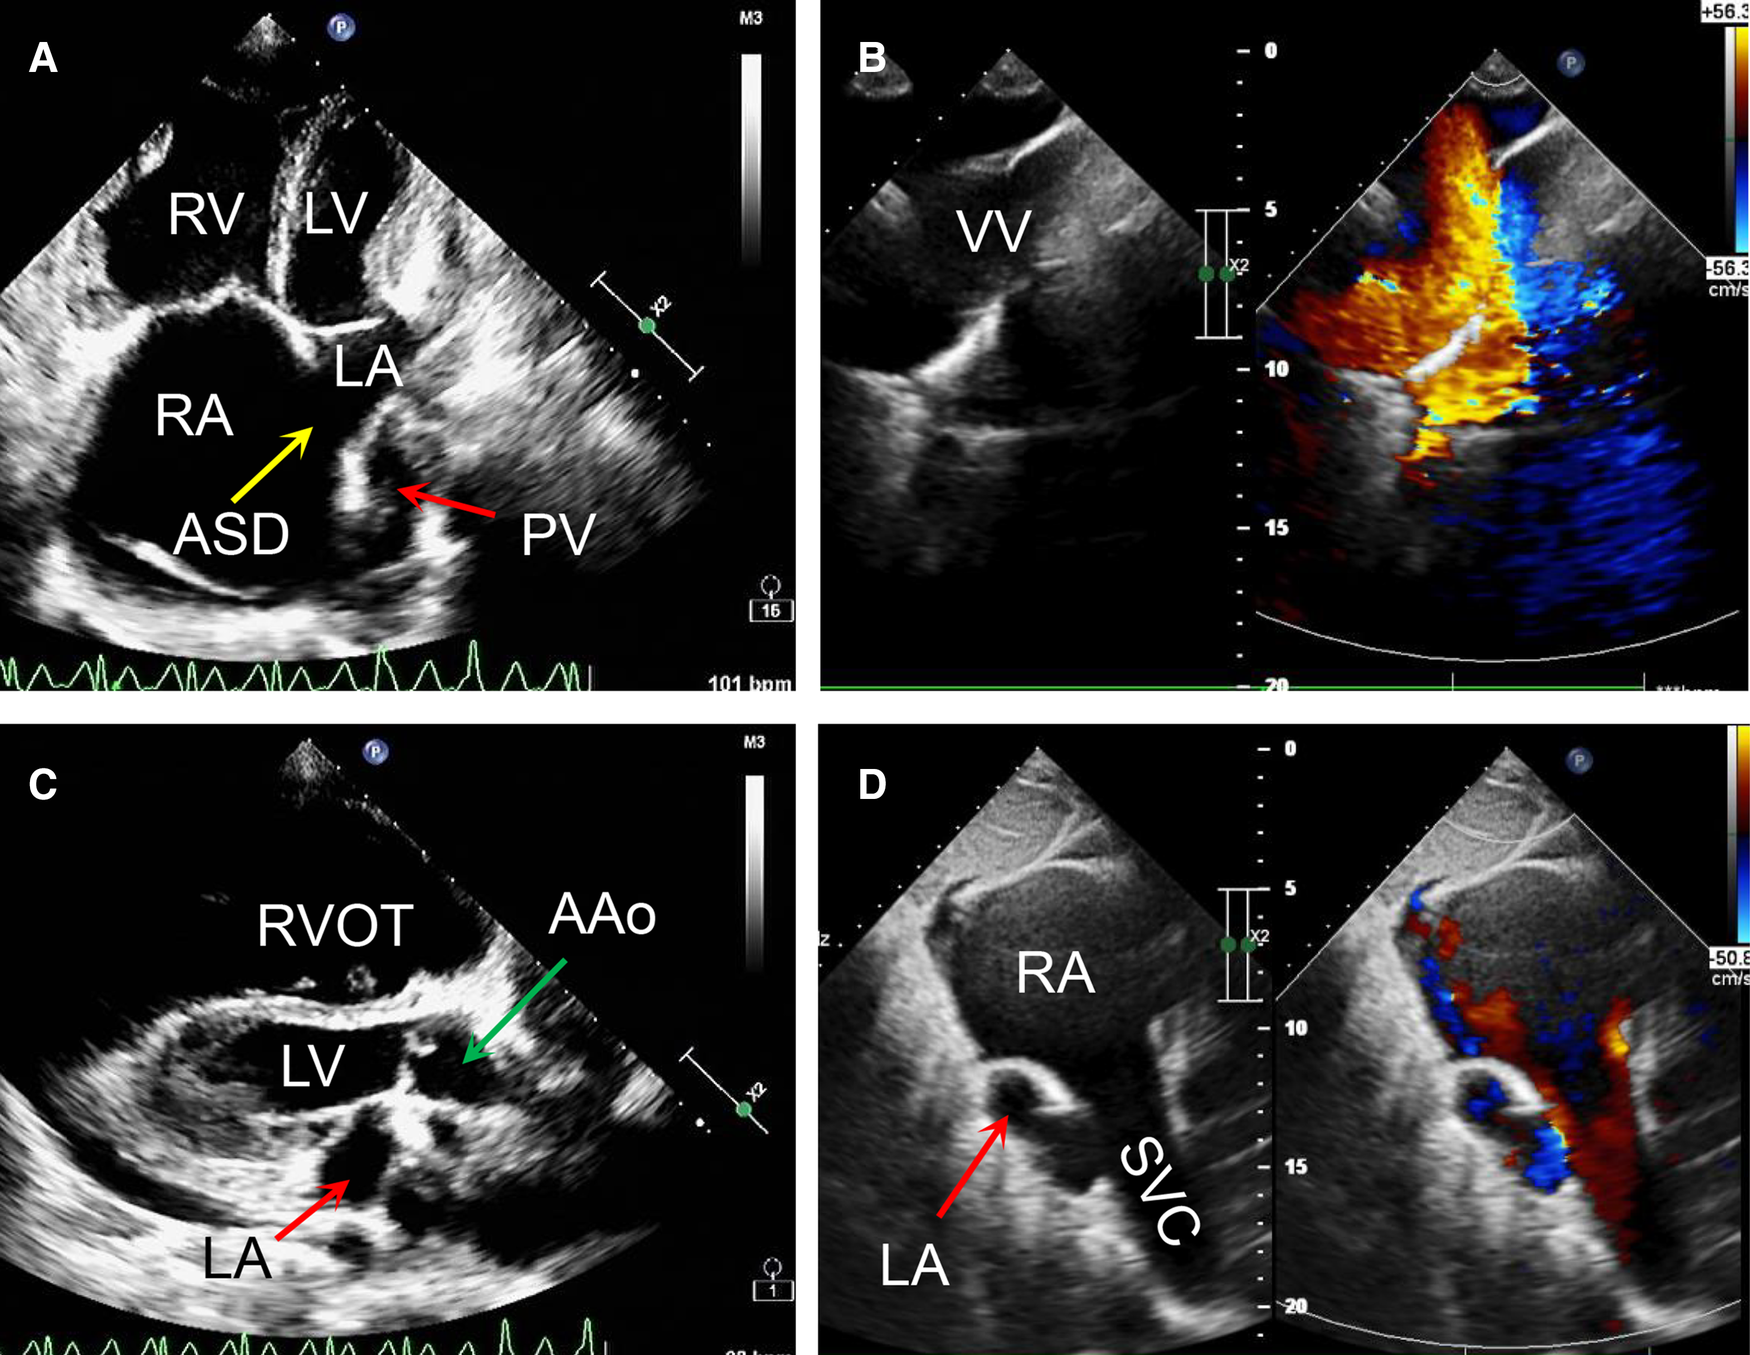

On the other hand, a cardiac computer tomography angiography was performed. The three-dimensional reconstruction figure showed that the entire left and right pulmonary veins were not directly drained into the LA but merged into a vertical vein (with a diameter of 44 mm) and flowed upward into the left brachiocephalic vein, IV and then into the SVC (Figure 1B, Supplementary Video S1). Transthoracic echocardiography revealed an atrial septal defect at the lower part of the interatrial septum with right to left shunt and ∼40 mm in diameter (Figures 2A,B). The RA and right ventricle (RV) were enlarged with right ventricular outflow tract hypertrophy. The pulmonary movement was significantly widened, the mean pulmonary arterial pressure was 55 mmHg, and the pulmonary peak velocity was 1 m/s with a pressure gradient and acceleration time of 4mmHg and 50 ms, respectively. The diameter of ascending aorta and the pulmonary trunk were 24 mm and 32 mm, respectively (Figure 2C). The entire four pulmonary veins returned to a vertical vein (around 23 mm), the IV, and the SVC (Figure 2D). Moderate tricuspid regurgitation was also detected. The LA, LV, RA, and RV sizes were 29 mm, 27 mm, 59 mm, and 51 mm, respectively. The LVEDV and LVESV were 28 ml and 10 ml respectively. The EF was 64%, while CO was 2.2 L/min.

Figure 2

Transthoracic echocardiography preoperatively revealed that a right to left atrial septal shunt was detected with the diameter of around 40 mm (A,B); the ratio of ascending aorta to the pulmonary trunk was 24:32 (C); the left and right pulmonary veins returned to a vertical vein then innominate vein and the superior vena cava. (D) AAo, ascending aorta; ASD, atrial septal defect; LA, left atrium; LV, left ventricle; PV, pumonary vein; RA, right atrium; RV, right ventricle; RVOT, right ventriclar outflowtract; SVC, superior vena cava; VV, vertical vein.